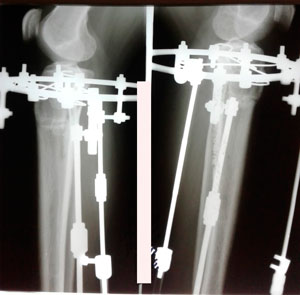

Дата операции - 07.05.2019г.